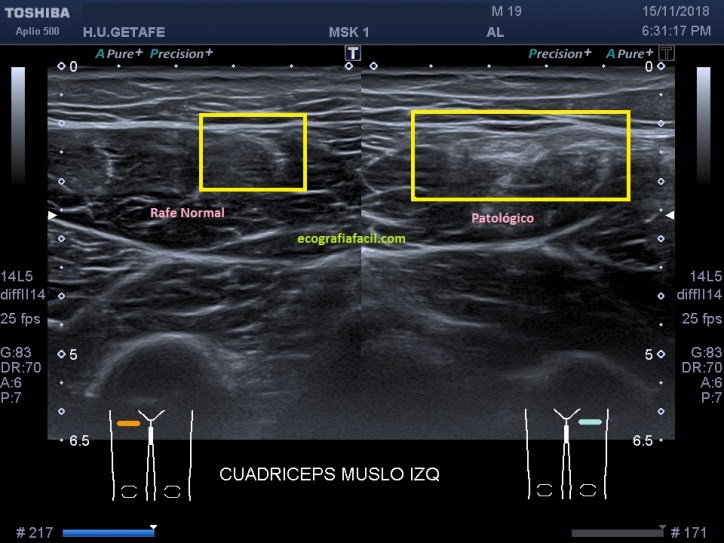

Comparando ambas regiones anteriores del muslo, a la altura de la región afectada vemos la diferencia de calibre de ambos rectos anteriores. Incluso en la imagen 6, realiza el paciente una contracción isométrica donde vemos que aumenta la diferencia de calibre con respecto a la misma imagen en relajación, imagen 5.

Comparar con el lado contralateral normal en este caso es revelador, en el lado normal vemos un tendón intramuscular normal, en el lado afectado y coincidiendo con la zona de dolor, una imagen alterada de este tendón intramuscular.

Comparing both anterior regions of the thigh, at the height of the affected region we see the caliber difference of both anterior straight. Even in image 6, the patient performs an isometric contraction where we see that the caliber difference with respect to the same image in relaxation increases, image 5.

Comparing with the normal contralateral side in this case is revealing, on the normal side we see a normal intramuscular tendon, on the affected side and coinciding with the area of ​​pain, an altered image of this intramuscular tendon.